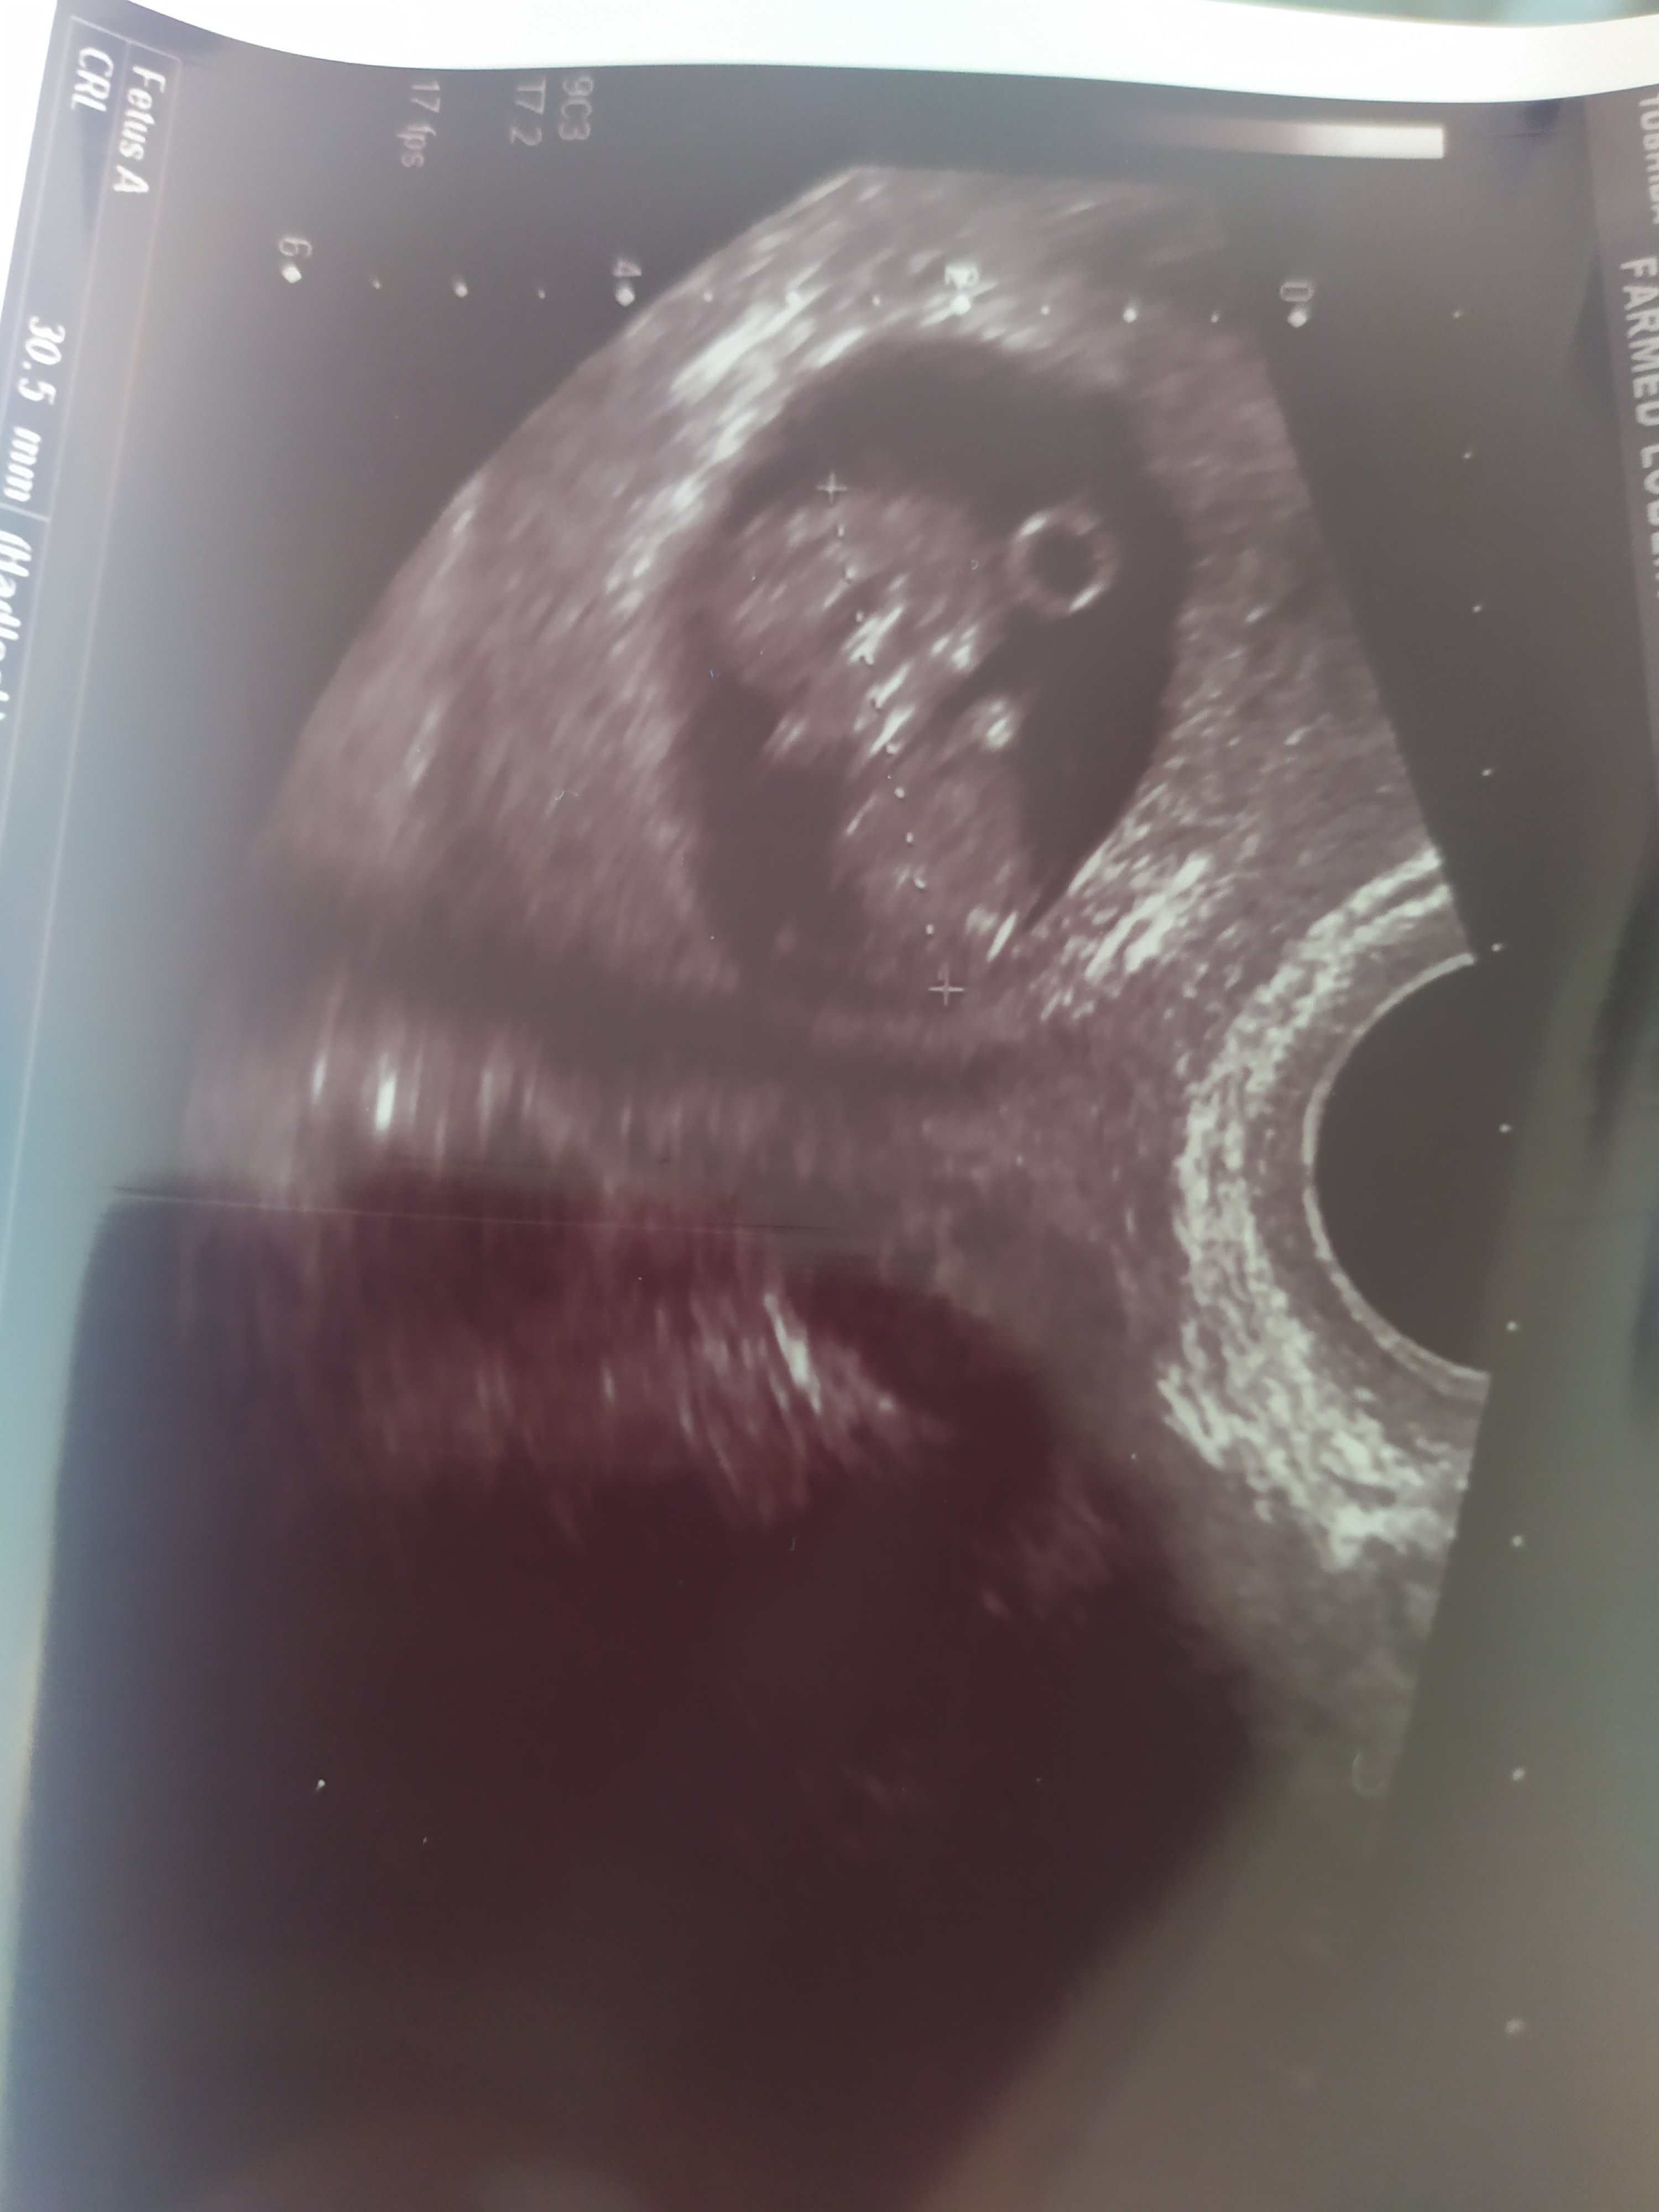

Piekny maluch!

Pieknie Dziecie❤ rośnie ! Gratulacje, wez co lekarz to pomysł! Jedna mi mowi brac luteine druga będziemy kończyć z progesteronem!Hej, ja już po wizycie, serduszko pięknie bijecałe 3 cm bąbla, z OM wychodzi 9+6 a z usg 10+0 . Pani doktor stwierdziła że mam też ognisko ablacji o wymiarach 15na 10 mm i mogę poronic

Zobacz załącznik 1175130